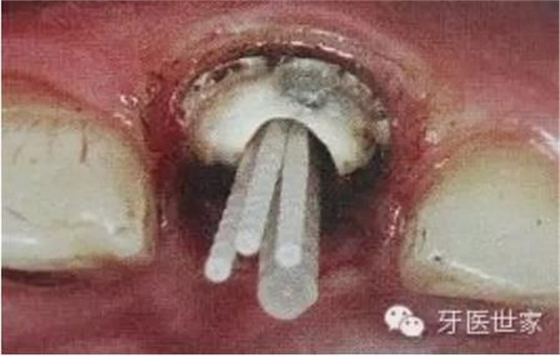

一般纖維樁使用數(shù)目要根據(jù)根管的粗細和牙體缺損范圍來設(shè)計,像牙膠尖根充一樣,在主尖周圍可以放置輔尖。

后牙一般按照牙體缺損范圍來設(shè)計,一般2到4個足夠了。